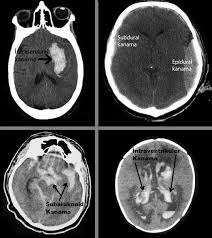

Subdural Kanama Nedir?

Subdural hematom, beynin yüzeyinde, duramater adı verilen koruyucu zarın hemen altında meydana gelen bir kan pıhtısıdır. Subdural kanamada, kan sızıntısı genellikle toplardamardan kaynaklanır ve yavaş ilerler, dolayısıyla belirtilerin ortaya çıkması bazen günler hatta haftalar alabilir. (Epidural kanamada, sızıntı bir atardamardan kaynaklanır, dolayısıyla belirtiler hızlı bir şekilde gelişir.)Ancak bazen çok kısa sürede büyük boyutlara ulaşan subdural kanamalar acil bir şekilde teşhis ve tedavi edilmezse, ölüm söz konusu olabilir.

Subdural Kanamanın Tanısı Nasıl Konur?

Kafa travması gibi acil durumlarda Bilgisayarlı tomografi ile tanısı konulurken geç belirti veren kronik subdural hematomlarda manyetik rezonans (MR) ile tanısı konulur.